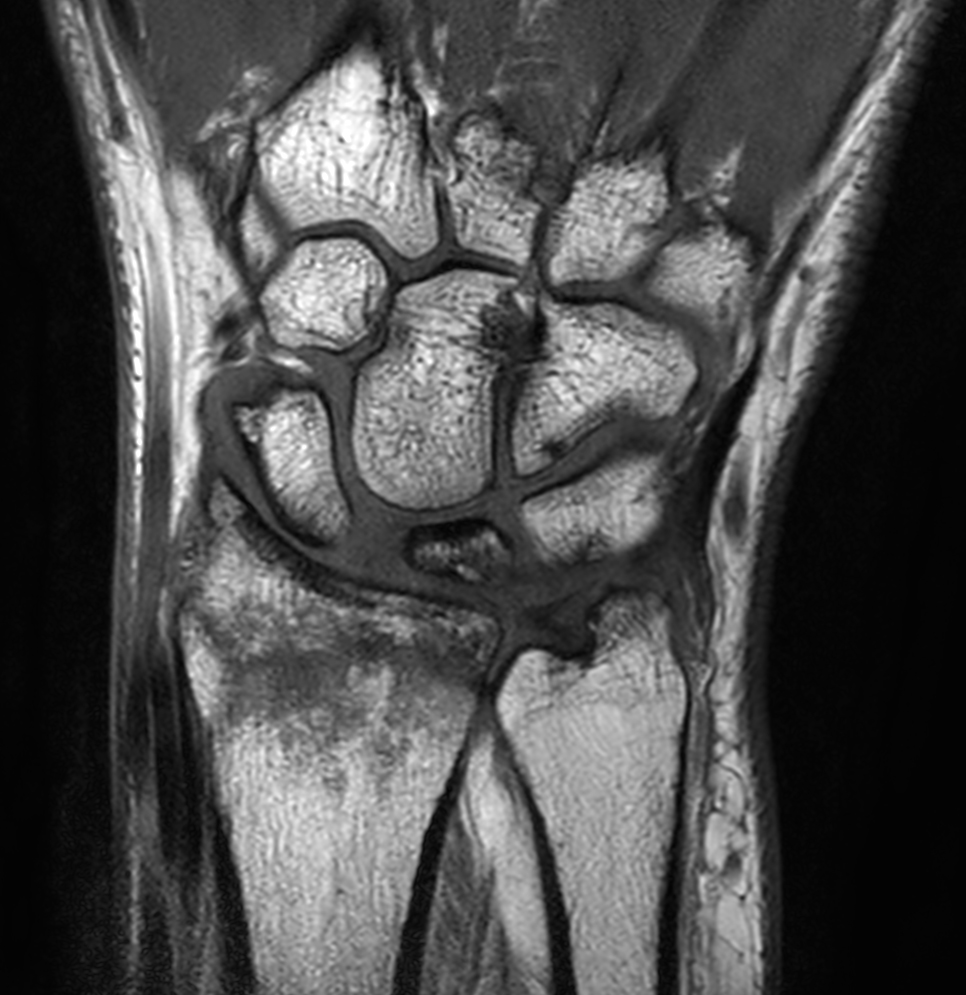

Patient with a wrist fracture. Compressed SENSE is used in all sequences, reducing the scan time while maintain equal image quality compared to scans without Compressed SENSE. 3D sequences have been added to this ExamCard with a comparable in-plane resolution but much thinner slices. Due to the shorter scan times that can be achieved thanks to Compressed SENSE, these 3D sequences could potentially replace the 2D sequences providing more confidence in making the diagnosis.

2D Coronal T1w TSE